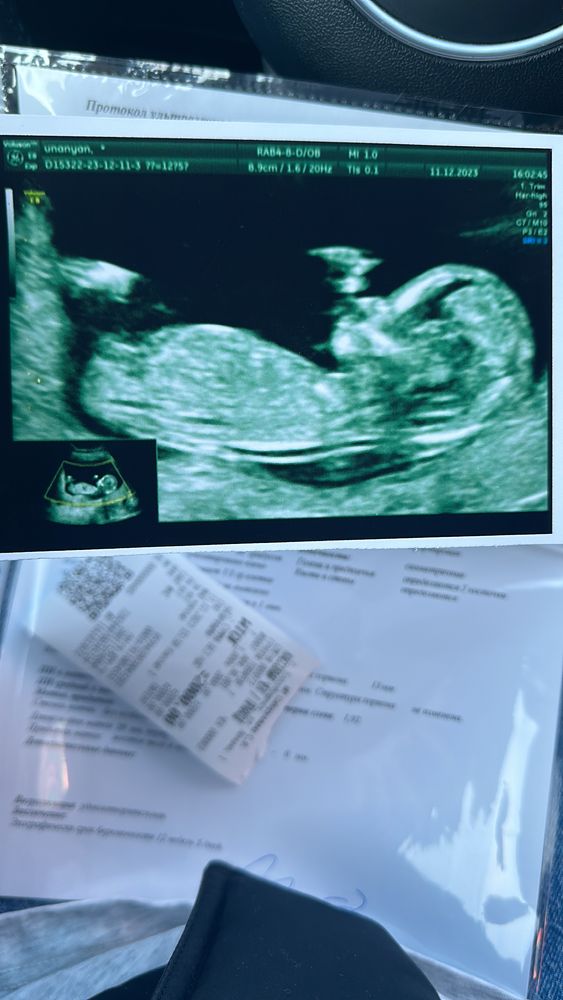

Пол малыша

Девочки последние месячные 25 сентября. Думала что нам уже 11 неделя Сегодня ходила на скрининг. Скрининге сказали что 9-10 недель. Пол малыша хотела узнать. Сказали наверное девочка. Через 15 дней приходит. Кто на каком недели узнал пол малыша